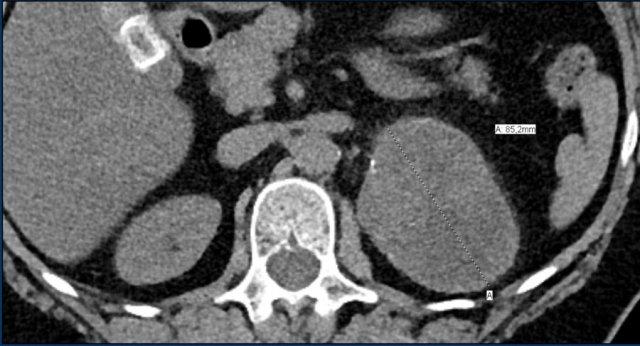

Các hình ảnh cho thấy u tình cờ tuyến thượng thận hai bên được phát hiện ở bệnh nhân 64 tuổi được chụp CT để phân tích phình động mạch chủ bụng.

Hình chụp pha động mạch cho thấy các tổn thương hai bên với tỷ trọng 50 HU.

Trên CT không tiêm thuốc thực hiện vài ngày sau, tỷ trọng ở cả hai tuyến thượng thận đều dưới 10 HU, xác nhận đây là các u tuyến giàu lipid.